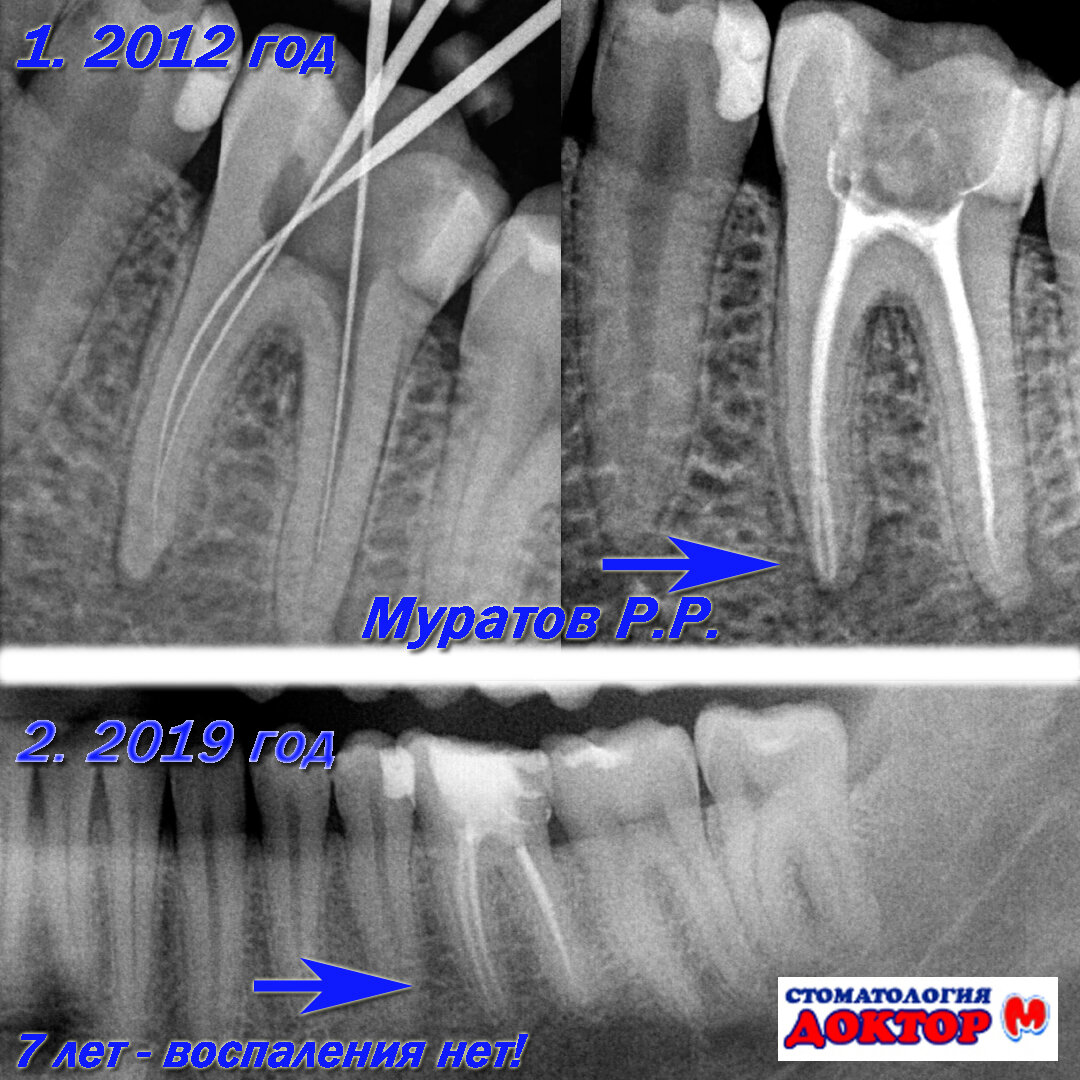

Перелечивала здесь два зуба, шестерки, очень сложные оказались, до этого два доктора сказали что не справятся. У Рустама получилось отлично, каналы вылечены, зубы спасены. А это самое главное. Спасибо, доктор!

Регулярно лечусь. Не менее 5 лет. Началось все с того что спасли мне зуб который другие рекомендовали удалить. Зуб все еще на своем месте